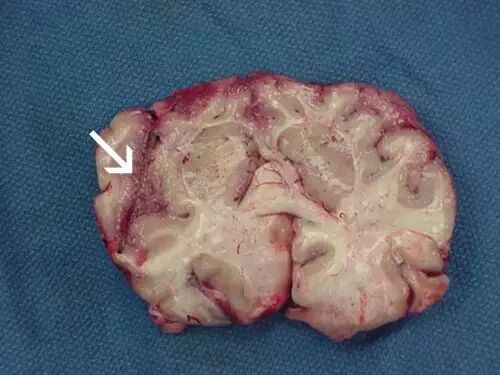

图为显微镜下观察到的、经荧光抗体染色的福氏内克尔变形虫耳稃。图源:美国病症掌控与预防中心 假如上述噬肉虫和引致组织坏死的病原体还不足以让你毛骨悚然,不妨接着往下看:自然界还存在一类能霸占人类大脑的微微生物。福氏内克尔变形虫耳稃(Naegleria fowleri)极其微小只有在显微镜下才能观察到,它生活在温暖的淡水中,会从鼻腔进入消化系统。它透过鼻窦膜进入大脑嗅球,并在此繁殖、扩散,同时吞食大脑组织。

变形虫充病毒感染的额叶皮质出现的坏死和脑出血 大脑病毒感染这些恐怖的变形虫虫后会患上原发性变形虫微血管病毒性,从而引致大脑水肿,甚至还有极高几率的致死可能。然而,有些人病毒感染福氏内克尔变形虫耳稃后还是活了下来,其中包括一位12岁的阿肯色州小姑娘。2012年,她在当地一个水上公园病毒感染了食脑变形虫虫,与病魔顽强抗争后,她康复了。当时,包括她在内,世界上只有三个人病毒感染食脑变形虫虫后还能活下来。  fill=%23FFFFFF%3E%3Crect x=249 y=126 width=1 height=1%3E%3C/rect%3E%3C/g%3E%3C/g%3E%3C/svg%3E)